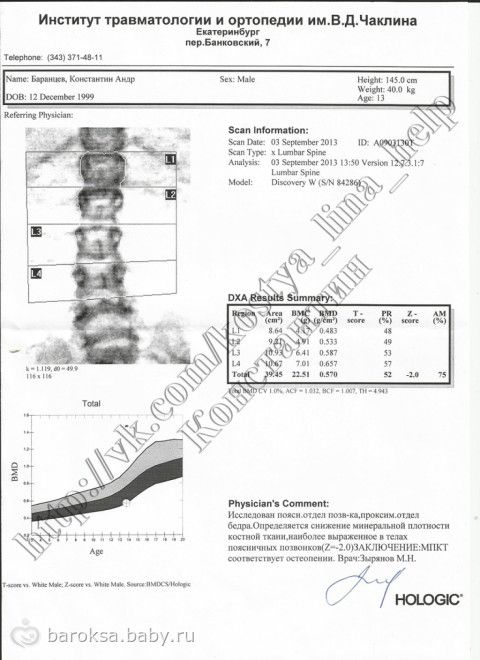

Добрый вечер, всем! Прошу прощения, что пишу чуть-чуть с опозданием. Часть нашего обследования уже позади. 3 сентября, съездили в Екатеринбург и успели сделать все, что запланировали. Сначала, в НИИ ортопедии, провели Костику денситометрию — исследование костной ткани на определение ее минеральной плотности. Обследовали поясничный отдел позвоночника и проксимальный отдел бедра. Заключение — «Определяется снижение минеральной плотности костной ткани, наиболее выраженное в телах поясничных позвонков. МПКТ соответствует остеопении». Не смотря на то, что обследование стоит 690 рублей, нам сделали его бесплатно. Потом, поехали в «Бонум», на электронейромиографию. Оказалось, что ЭМНГ делает врач-невропатолог, к которому мы записались на консультацию 5 сентября. И она согласилась после обследования принять нас. Не надо ехать еще раз!!! ЭМГ — это комплекс исследований для оценки работы мышц и качества передачи нервных импульсов по периферическим нервам и проводящим путям головного и спинного мозга. Делали только Ангелинке. Заключение — «Признаки надсегментарной патологии в правой нижней конечности». После консультации невролога, добавилось — «Тонус мышц повышен в правых конечностях. Пирамидальная недостаточность, грубее справа, контрактура правого т/б сустава». Как и Костюшке, необходимо проходить курсы лечения и реабилитации, не менее 2-ух раз в год. За обследование заплатили — 696 рублей, за консультацию — 910 рублей. Ну, и 2500 рублей, за такси. К сожалению, другой вид транспорта, нам пока по-прежнему не доступен.

Денситометрия: